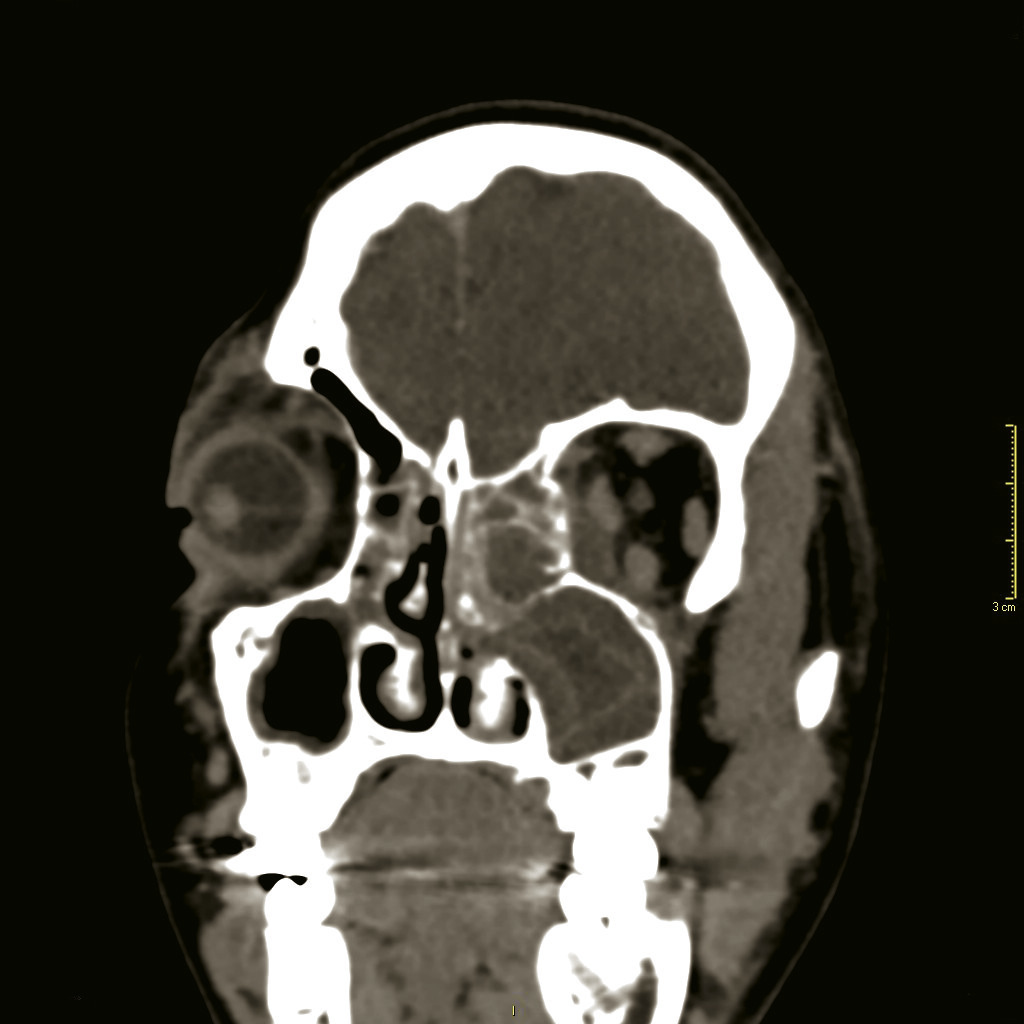

Une tomodensitométrie avec injection de produit de contraste est indiquée d’emblée si l’œil n’est pas ouvrable spontanément, s’il y a une limitation des mouvements de l’œil ou une exophtalmie, mais aussi chez l’enfant de plus de 9 ans ou en cas d’absence d’amélioration clinique après 24 heures de traitement.4 Elle confirme l’ethmoïdite et surtout recherche une complication intracrânienne, particulièrement un abcès sous-périosté intra-orbitaire (fig. 3 ).

Une tomodensitométrie avec injection de produit de contraste est indiquée d’emblée si l’œil n’est pas ouvrable spontanément, s’il y a une limitation des mouvements de l’œil ou une exophtalmie, mais aussi chez l’enfant de plus de 9 ans ou en cas d’absence d’amélioration clinique après 24 heures de traitement.4 Elle confirme l’ethmoïdite et surtout recherche une complication intracrânienne, particulièrement un abcès sous-périosté intra-orbitaire (